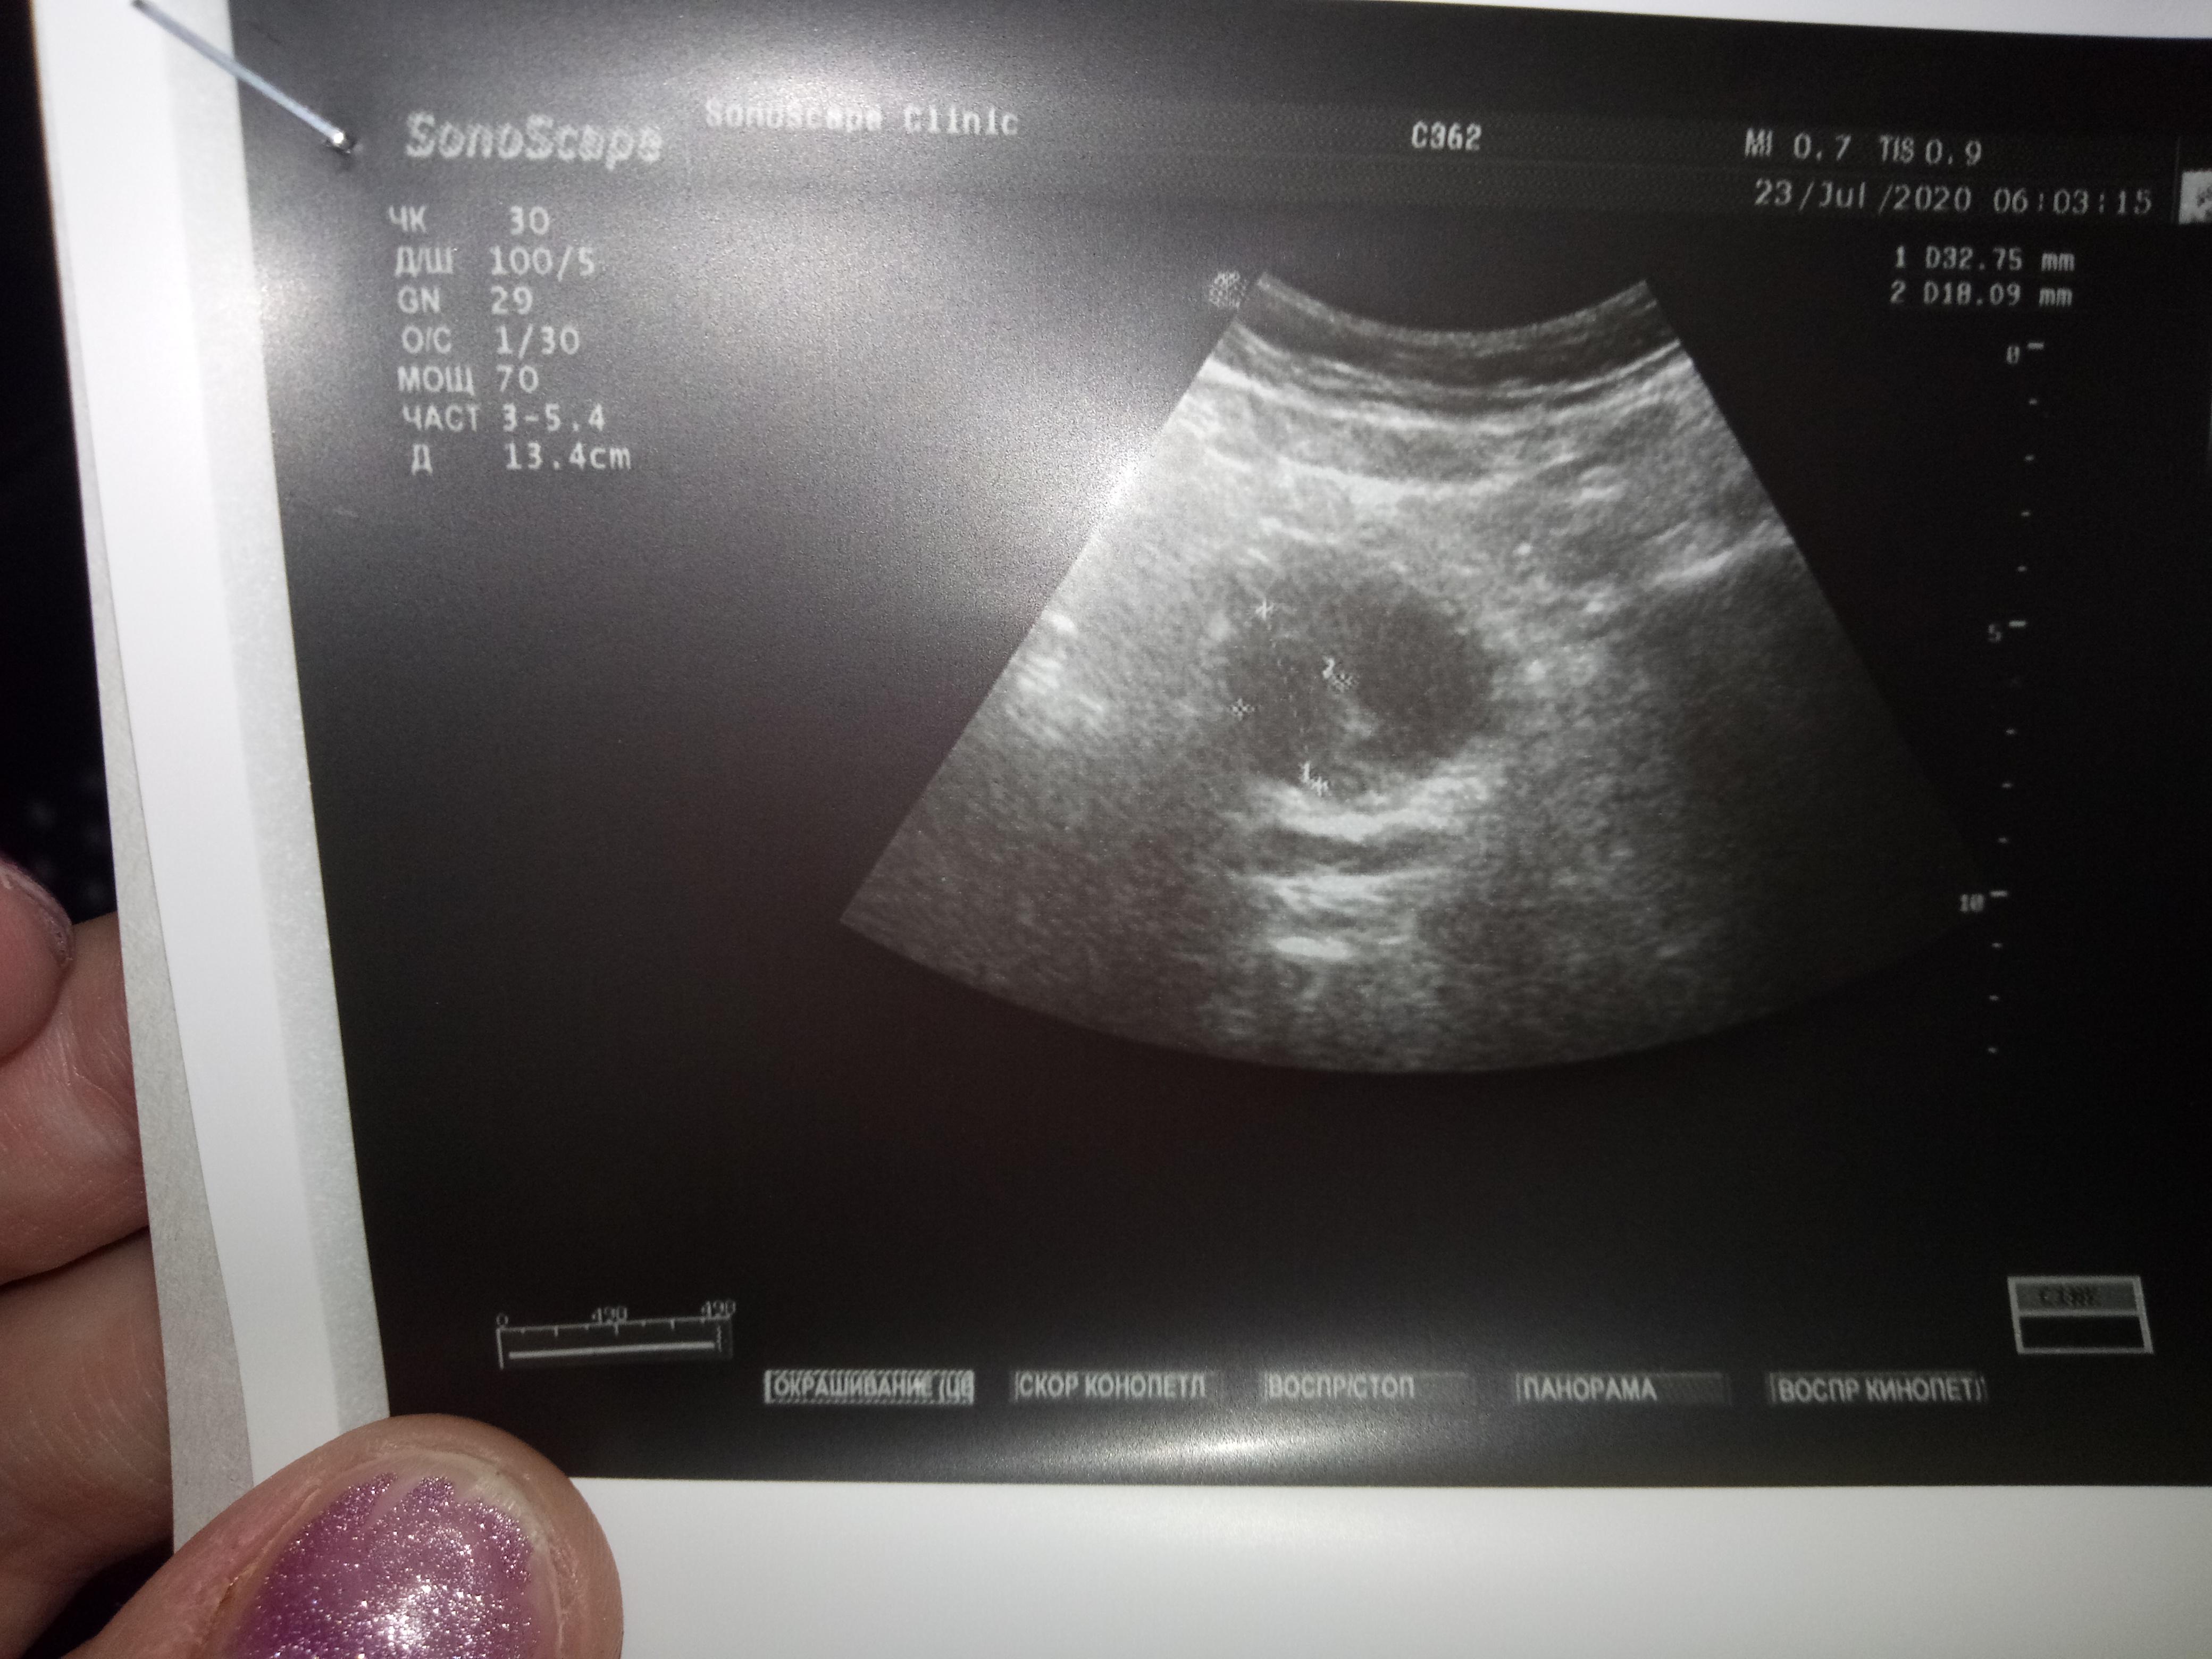

Пожалуйста,можно ли по данным анализам назначить лечение? Какая стадия рака?При отказе на операцию возможен ли прогноз,продолжительность жизни?

анализы отца,пожалуйста подскажите лечение,госпитализироваться отец отказался,боиться.Пожалуйста подскажите лечение,возможно ли оно?